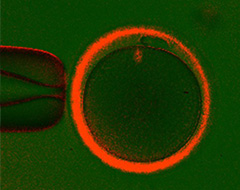

卵子にやさしいピエゾICSI

『おち夢クリニック名古屋』では、ピエゾICSIを導入しています。これは先端がフラットなガラス管に微小なパルスをかけることによって卵細胞膜に小さな穴を開け、そこから精子を注入する方法です。この方法は、卵子への物理的ストレスが小さくなり、安定した受精成績が得られると考えています。

以前は卵子を固定し、そこに極細の針を刺し入れていました。卵子は、透明帯という膜に守られていますので、それを針で刺し、押し切るような形で精子を注入していきます。そのため針の先端が卵細胞膜に押し込まれたような状態になり、これが卵細胞膜を壊してしまう原因にもなっていました。

ピエゾICSI。

先端がフラットなガラス管に微小パルスをかけて卵細胞膜に穴を開けます。

従来のICSIでは、スパイクのついたガラス管を卵細胞に刺して行います。